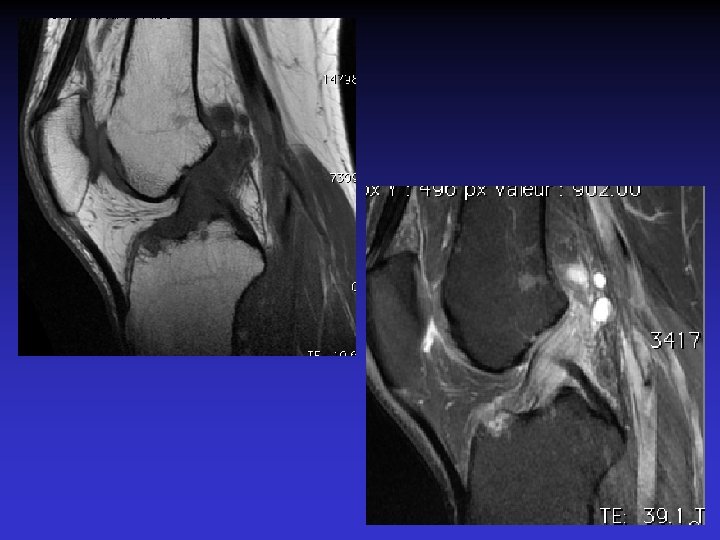

DIAGNOSTIC DIFFERENTIEL • Rupture du LCA • Tumeur synoviale

RUPTURE DU LCA

SVN